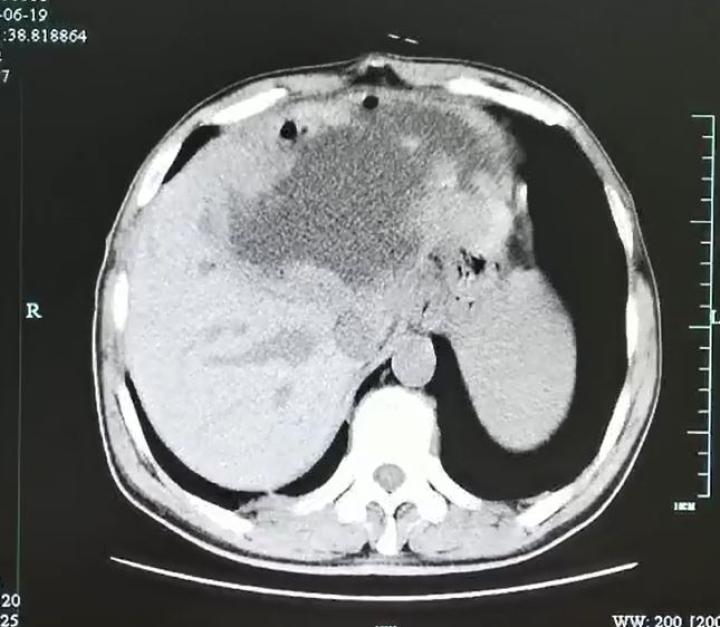

入院后腹部CT检查发现肝脓肿壁上长了很多肿瘤样的结构,而且壁很厚。看来这个肝脓肿不简单。

为了让脓球变小,进一步追查“元凶”,医生在超声指引下给谢师傅做了脓球的穿刺引流。结果大量的灰白色脓液被顺利引出,但是经过一系列的检查后,却没有发现细菌、真菌、结核和恶性肿瘤的“踪影”。那谢师傅到底得了什么病呢?